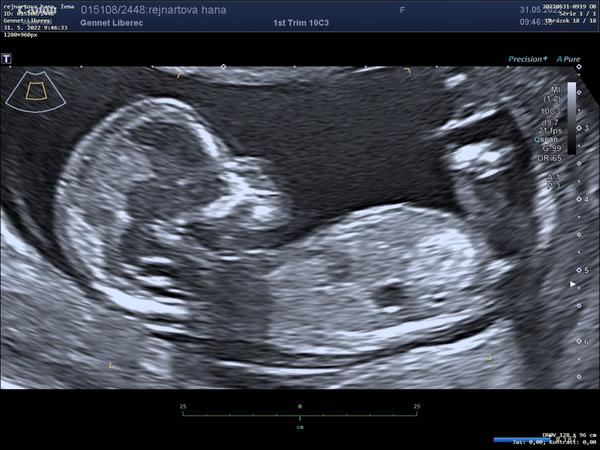

@katherine177 aspon, ze tak, ikdyz mi to je teda moc lito. Je to nespravedlive. Ja dnes po kontrole 8+3 Mam prukazku termin na screening a melo by byt vse jak ma…jen cysta stale vetsi a vetsi. Moc dekuji za optani